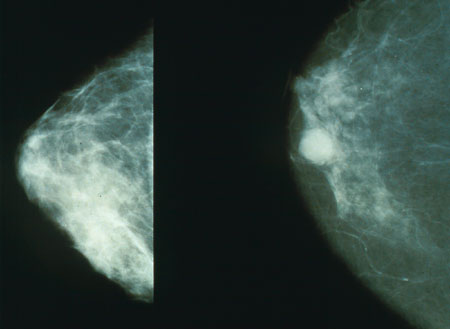

As only a minority of suspicious mammograms actually lead to a cancer diagnosis, the researchers said elastography can be used to pinpoint possible tumours throughout the body, including the breast.

"Ultrasound elastography could be an excellent screening tool for women who have suspicious mammograms, but only if the results are properly interpreted," the study said.